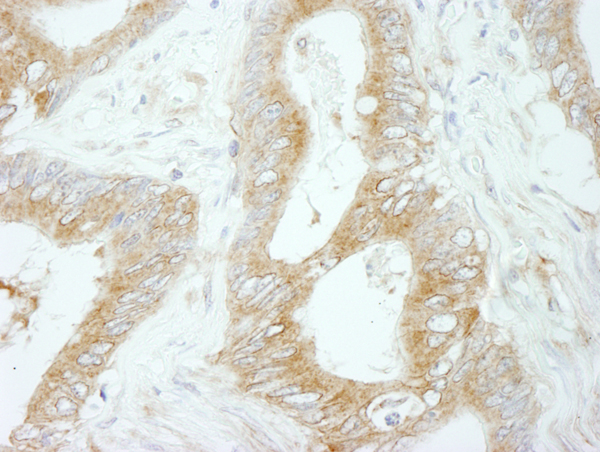

IHC (Immunohistochemistry)

(Detection of human Flightless-1 by immunohistochemistry. Sample: FFPE section of human colon carcinoma. Antibody: Affinity purified rabbit anti-Flightless-1 (Cat. No. AAA213965) used at a dilution of 1:250. Detection: DAB)